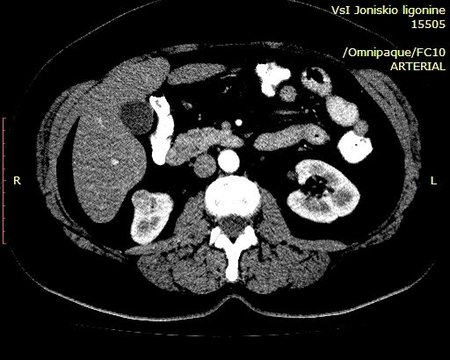

Выполнена КТ с контрастированием.

Гистология - ангиомиолипома (выполнена резекция опухоли).